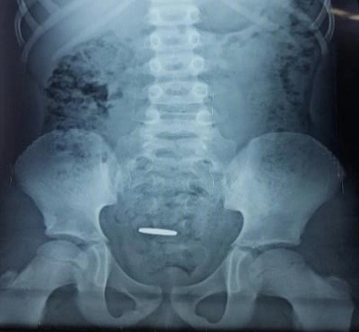

Quan un nen s'empassa accidentalment un objecte, és important actuar amb precaució. La ingesta de cossos estranys és comú en nens petits, amb monedes sent l'objecte més freqüent. En la majoria dels casos, aquests objectes passen naturalment a través del sistema digestiu. No obstant això, alguns objectes requereixen endoscòpia o extracció quirúrgica. La ubicació de l'objecte en l'esòfag, l'estómac o l'intestí prim determina el risc i el tractament adequat. La seguretat i l'atenció mèdica són fonamentals en aquests casos.

La ingesta d'un cos estrany és el pas al tracte digestiu (esòfag, estómac i intestí) d'un objecte. En la majoria de casos es tracta d'una ingesta accidental en nens en edat preescolar o escolar, registrant la major incidència al voltant dels tres anys. En aquests casos les monedes són el cos estrany més freqüentment ingerit. Altres cossos estranys freqüents són agulles, parts de joguines i balins.

El 80% s'eliminen espontàniament, un 19% necessiten endoscòpia (segona causa més freqüent d'endoscòpia en l'edat pediàtrica) i un 1% extracció quirúrgica.

La probabilitat de produir algun tipus de repercussió sobre la salut depèn de les característiques de l'objecte ingerit. La seva grandària, forma i composició determinen, en primer lloc, la seva capacitat de progressió al llarg del tracte digestiu i, en segon lloc, el possible dany local que poguessin causar per mecanismes físics o químics.

Cossos estranys en estómac

És la localització més freqüent en el moment del diagnòstic (60%). En nens més grans, objectes de menys de 2 cm d'amplada i fins a 5 cm de longitud poden sortir de l'estómac sense dificultat. En nens petits i lactants, el límit de longitud és de 3 cm.

És recomanable extreure aquells cossos estranys amb alt risc de complicacions: grandària superior a l'indicat anteriorment, objectes punxants i/o tallants (agulles, agulles, vidres,...), piles de botó i imants, en el cas d'haver-ne ingerit diversos.

En la resta dels casos, que suposen la majoria, els cossos estranys s'expulsaran amb facilitat i no és necessària l'hospitalització. S'aconsella dieta rica en fibra i vigilar els excrements buscant l'objecte i s'indicarà tornar al nen a urgències si no l'expulsa en dues setmanes o si apareix dolor abdominal, vòmits o sagnat pel recte. No està indicada l'administració de laxants, encara que ocasionalment es poden utilitzar olis minerals.